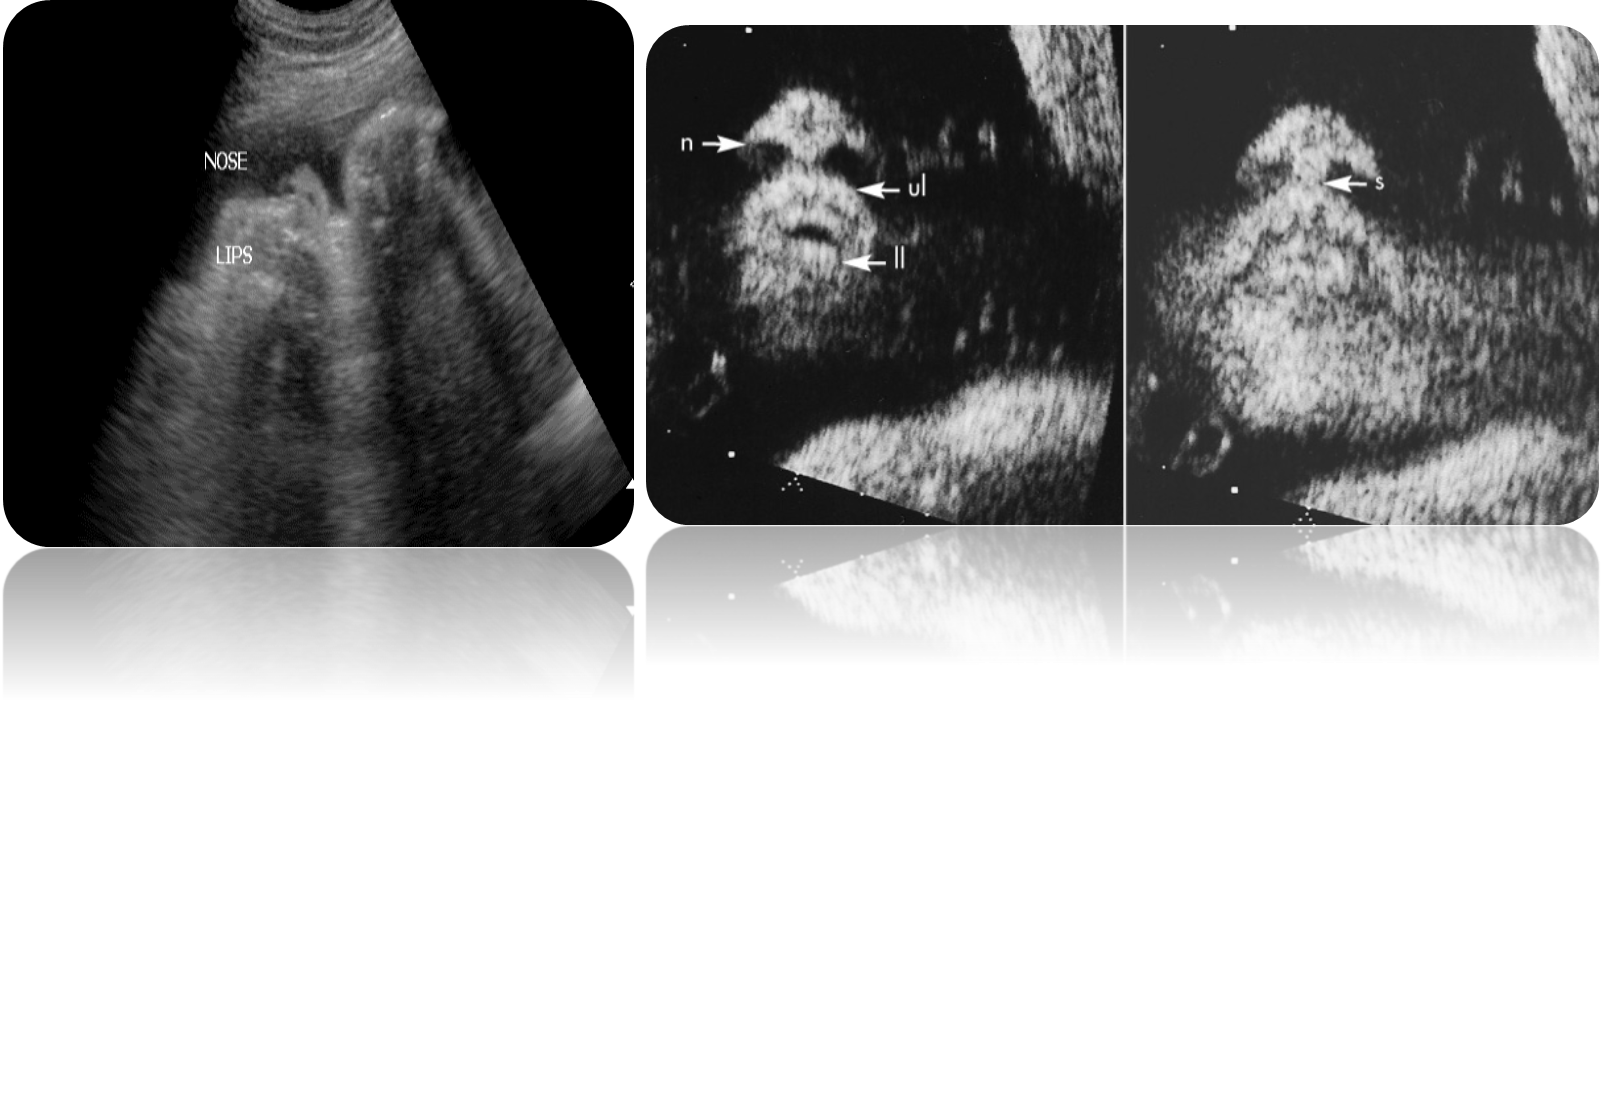

What are these images showing?

Midface Hypoplasia or Maxillary Hypoplasia

What is this image showing?

Absent nasal bone What